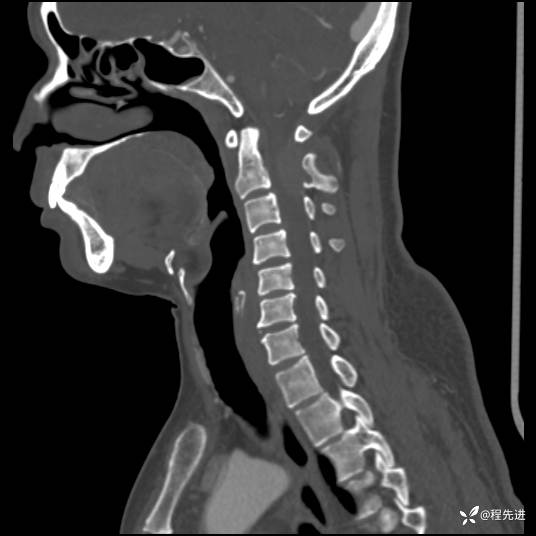

CT平扫+增强: